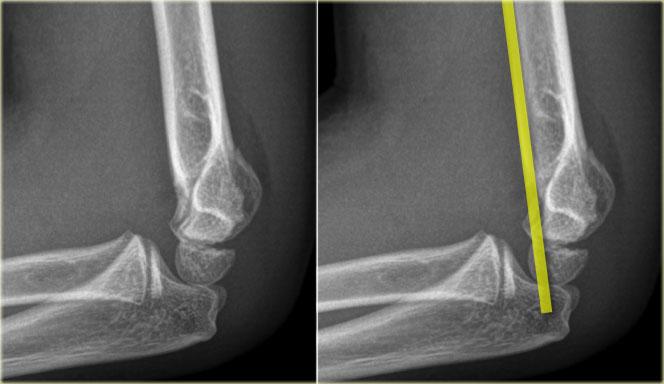

Radiographs of elbows at different ages. The Anterior Humeral line goes through the middle third of the capitellum .

Đường Humeral trước.

Một đường kẻ trên phim chụp nghiêng dọc theo bề mặt trước của xương cánh tay phải đi qua một phần ba giữa của chỏm con.

Đường này được gọi là đường Humeral trước.

Trong các trường hợp gãy xương trên lồi cầu, đường Humeral trước thường đi qua một phần ba trước của chỏm con hoặc ở phía trước chỏm con do sự uốn cong ra sau của đoạn xương cánh tay xa.

Ở bên trái, đường thẳng cánh tay trước đi qua một phần ba trước của chỏm con.

Điều này cho thấy các lồi cầu bị di lệch về phía sau (tức là gãy trên lồi cầu).